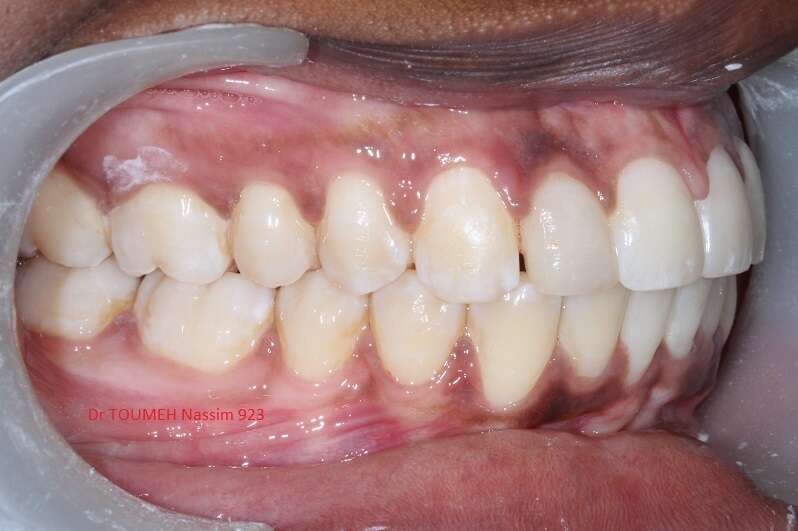

Latérales naines et orthodontie

la forme des dents influence grandement l’esthétique du sourire

La malformation des incisives latérales en est l'illustration

Le traitement consiste à redresser les dents à l'aide d'un appareil orthodontique (Multiattaches) et à redonner une forme normale aux dents malformées.

Dans ce cas présenté des couronnes provisoires en résines ont été posées.

Après